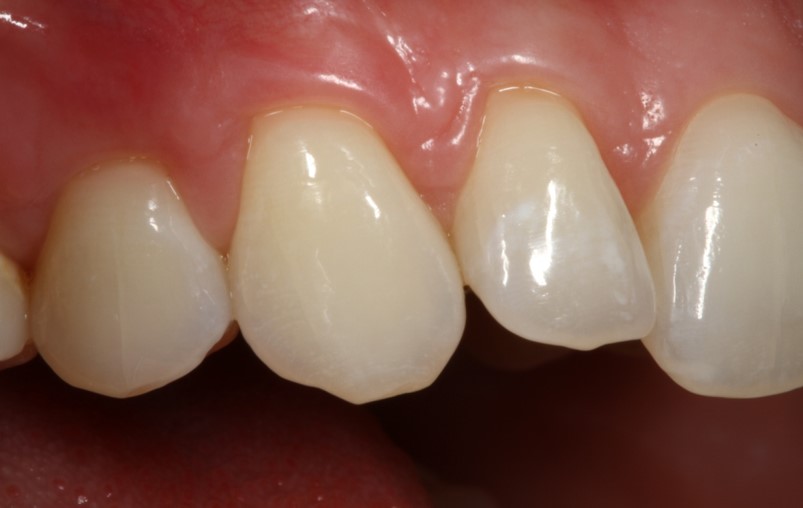

06/06 - Clinical situation 18 months post-operative.Multiple gingival recessions treated with the modified coronally advanced flap in conjunction with mucoderm® - Prof. Dr. Dr. A. Kasaj